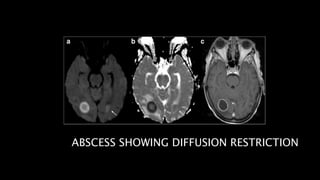

Affects cortex in NONVASCULAR distribution

ABSCESS SHOWING DIFFUSION RESTRICTION

• #58 Right occipital pyogenic abscess showing marked diffusion restriction within the core on DWI and ADC maps and a peripheral enhancing pattern on T1 post gadolinium